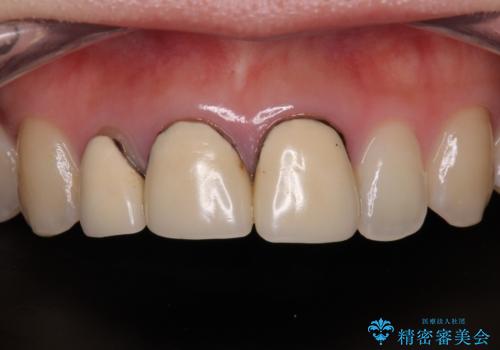

前歯の黒い縁を綺麗にしたい 前歯のオールセラミック

- 以前に装着した前歯のクラウンの縁が見えていることを気にして来院された患者様です。

根尖部に病変のある2歯は事前に根管治療を行い、オールセラミッククラウンにて補綴することとしました。